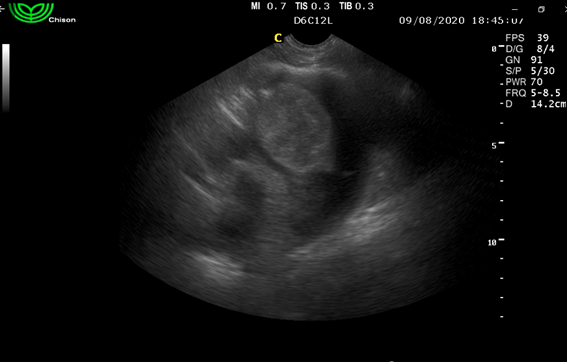

Paciente canino hembra, nacida en Montevideo (Uruguay), de la raza Ovejero Alemán de 8 años, de 35 kg de peso vivo, esterilizada. Presentaba su plan sanitario vigente y se alimentaba con comida balanceada Premium (marca Equilibrio) sin antecedentes de enfermedades previas. Comenzó con decaimiento, dificultad para incorporarse, sensorio deprimido y angustia respiratoria. Consultó en otra clínica en la que se realizó una ecografía de tórax constatando un derrame pericárdico de origen desconocido. Se drenó la colecta pericárdica, según relato anamésico del tutor, mediante punción pericárdica (pericardiocentesis), hasta que el animal recuperó su condición previa a la instauración del cuadro clínico. Se dio de alta con estrictas indicaciones que debería consultar si surgían los mismos síntomas. A los 5 días de este episodio, se realizó una ecocardiografía con un ecógrafo marca Chison en modo B, de urgencia en el Hospital Veterinario “La Carlota”, constatando la presencia de un tumor en la pared libre de la aurícula derecha justo en la unión con el ventrículo derecho de ecogenicidad mixta (figura 1).

En esa consulta se repitió la pericardiocentesis, obteniendo 150 ml de un líquido serosanguinolento, que no coaguló incluso hasta haber transcurrido más de una hora. Se remitió una muestra al laboratorio Vetin (Montevideo) para estudio citológico. El informe citológico dio un resultado compatible con hemangiosarcoma, la celularidad encontrada fue de células del tipo endotelial prominentes de gran tamaño con anisocitosis, vacuolas intracitoplasmáticas, alterada relación núcleo citoplasma y presencia de mitosis (figura 2).